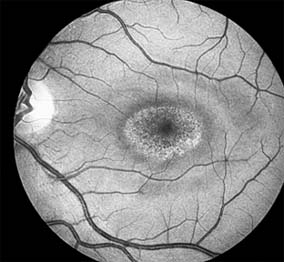

Nonexudative age-related macular degeneration is characterized by variable degrees of atrophy and degeneration of the outer retina, retinal pigment epithelium, Bruch's membrane and choriocapillaris. Of the ophthalmoscopically visible changes in the retinal pigment epithelium and Bruch's membrane, drusen are the most typical (Figure 10-1). Drusen are discrete, round, yellow-white deposits of variable size beneath the pigment epithelium and are scattered throughout the macula and posterior pole. With time, they may enlarge, coalesce, calcify, and increase in number. Histopathologically, most drusen consist of focal collections of eosinophilic material lying between the pigment epithelium and Bruch's membrane; they therefore represent focal detachment of the pigment epithelium. In addition to drusen, clumps of pigment irregularly dispersed within depigmented areas of atrophy may progressively appear throughout the macula. The level of associated visual impairment is variable and may be minimal. Fluorescein angiography demonstrates irregular patterns of retinal pigment epithelial hyperplasia and atrophy. Electrophysiologic testing in most patients is normal.

Figure 10-1

Figure 10-1: Age-related macular degeneration with discrete (small arrow) and large confluent (large arrow) macular drusen.